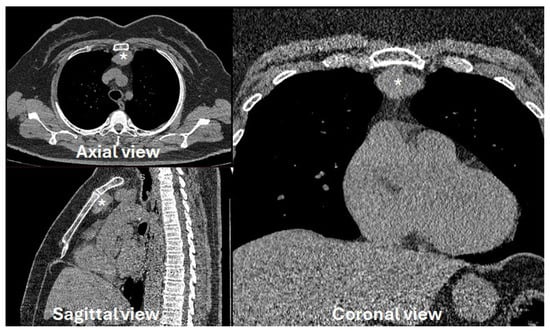

图1)。未对病变进行细针活检。经过多学科讨论,建议采用左侧入路的RATS根治性胸腺切除术。

图1. 多平面CT扫描显示,一名49岁非重症肌无力女性患者的左侧胸腺瘤(*)大小为35毫米。